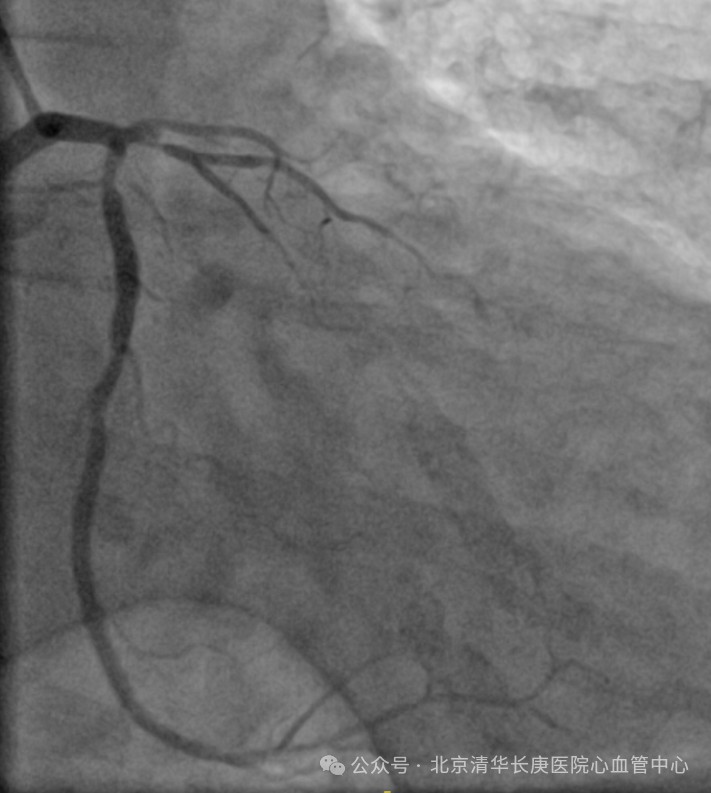

故事得从2024年元旦说起,伴随着一阵急促声,北京清华长庚医院急诊部接诊了一位突发喘憋伴一过性意识丧失的患者,急诊医师快速判断出患者存在心肌缺血及心衰表现,且合并晕厥,病情危重,遂请心血管内科急会诊。北京清华长庚医院心血管内科当天值班的佘飞主任、向伟主治医师迅速到场,详细询问后发现王阿姨患有高血压,糖尿病,高胆固醇血症多年,平素间断有胸闷症状。3个月前突发过明显胸痛1次,在家休息后缓解。此后逐渐出现活动量明显下降。当天因着急追公交车后突发喘憋伴一过性意识丧失紧急就诊。佘飞主任、向伟主治医师迅速判断出王阿姨患有冠状动脉粥样硬化性心脏病(简称冠心病),3月前突发急性心肌梗死后出现心功能不全,此次因为追公交车后出现了心衰急性发作伴晕厥。冠心病 心肌梗死非常常见,心力衰竭是心肌梗死后十分常见的并发症,严重影响患者的生活质量,也是导致反复住院甚至导致死亡的常见病因。为此,王阿姨被立即护送到心血管中心接受治疗。在佘飞主任、何榕主任及马志毅副主任医师、向伟主治医师的指导下、心血管中心医护团队为王阿姨精心制定了治疗和护理方案,超声影像团队的刘芳主任医师也为患者仔细查进行了超声心动图检查证实王阿姨的心脏出现了心肌梗死后的一系列典型改变(左心增大、室壁运动障碍、室壁瘤形成、心功能显著减低,左心室射血分数仅35%)。冠脉介入团队的耿雨主治医师随后为王阿姨进行造影检查发现王阿姨的三支冠脉均严重狭窄,其中左前降支近端100%闭塞。后续检查发现其心脏梗死面积大,冬眠心肌少。优化药物治疗后王阿姨的喘憋症状得到了显著缓解,但冠脉狭窄、心肌坏死及室壁瘤无法解决。

(患者冠脉造影)